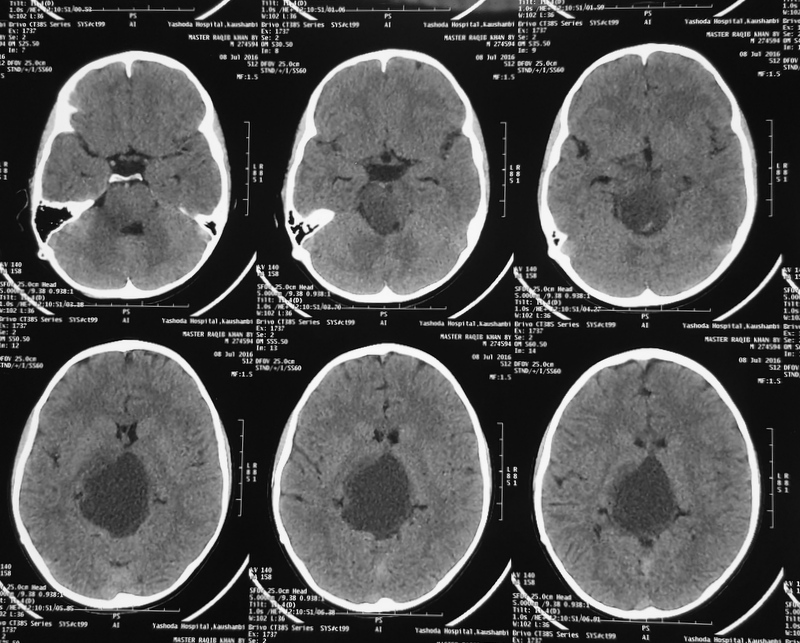

A 38-year-old-male was admitted with sudden onset of severe global headache and vomiting, followed by altereation in sensorium. CT brain showed subarachnoid and intraventricular hemorrhage (Fig 1). MRI brain revealed deep seated right sided thalamic hematoma due to ruptured internal carotid artery bifurcation aneurysm (Fig 2), confirmed by cerebral digital subtraction angiography (Fig 3). He underwent clipping of the aneurysm by transciliary supraorbital keyhole minicraniotomy (see video). Postoperative angiography showed complete occlusion of the aneurysm (Fig 4). When discharged ten days later, there was no neurological deficit (Fig 5).

Fig 1

(Fig 1)